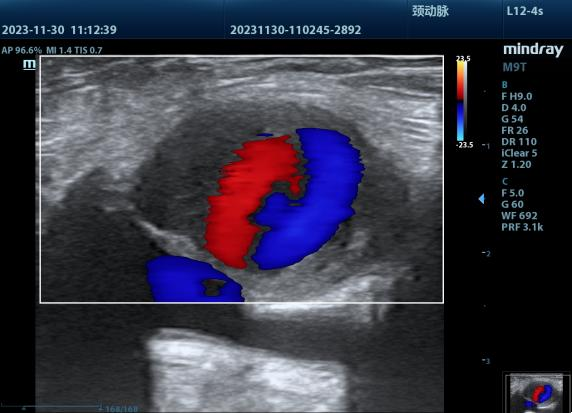

经过全面的检查,苏奶奶被确诊为右侧股动脉假性动脉瘤并血栓形成。这个瘤体大小约33*19mm,同时瘤体内可见血流往复信号,这意味着随时有破裂的危险,情况十分紧急,必须尽快进行治疗处理。

治疗前彩超(假性动脉瘤瘤体巨大)